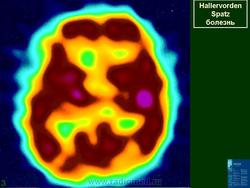

Галлервордена - Шпатца болезнь (J. Hallervorden, 1882-1965, нем. невропатолог; H. Spatz, совр. нем. невропатолог; син. ригидность прогрессирующая) - наследственная болезнь, связанная с нарушением обмена железа и липидов, проявляющаяся в возрасте 7-9 лет повышением мышечного тонуса, гиперкинезами, прогрессирующей деменцией, снижением зрения и пигментным ретинитом; наследуется по аутосомно-рецессивному типу.

Болезнь Галлервордена - Шпатца - наследственное заболевание экстрапирамидной системы, связанная с нарушением обмена железа и липидов и повреждением бледного шара и черной субстанции. Тип наследования аутосомно-рецессивный. При патоморфологическом исследовании характерным признаком является гиперпигментация бледного шара и черной субстанции. Обнаруживается пигментация коры полушарий большого мозга и таламуса. Пигмент находится внутри невронов и глиальных клеток, расположенных около сосудов; содержит железо (вместе с тем каких-либо нарушений обмена железа в организме не обнаружено). Наблюдаются утолщение и фрагментация аксонцилиндров в пораженных областях. Постепенно наступает дегенерация невронов коры полушарий большого мозга и мозжечка. Характеризуются нарастающей экстрапирамидной ригидностью, гиперкинезами (атетоз, торсионная дистония), затем развивается акинетико-ригидный синдром, пирамидная микросимптоматика, снижение интеллекта. Течение медленно прогрессирующее на протяжении 10 - 20 лет.

"Глаз тигра"-наглядно и красиво.